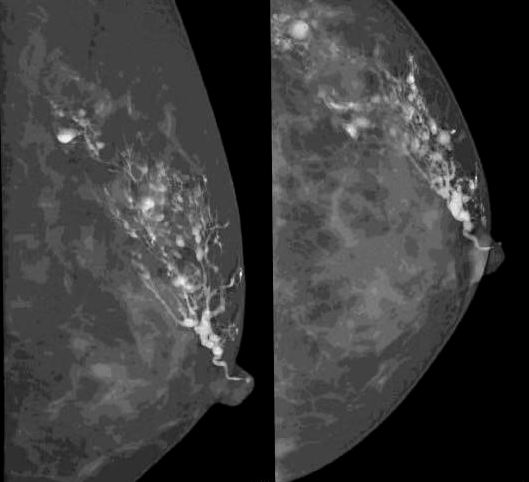

近年来,随着乳腺疾病逐渐增多,乳腺检查方法也日新月异,乳腺DR作为其中的一种检查方法应用较为广泛。日前,明光市中医院引进筛查和诊断乳腺疾病的“利器”——“联影-嫦娥3D”乳腺DR设备,能为广大群众朋友们提供精准的乳腺检查。

该设备具有高清、低剂量、断层三维融合数字成像的优势,可提高乳腺癌早期检出率并精准定位。

现代的乳腺X线检查设备不再是过去的二维成像,而是通过三维断层扫描,能更加清晰显示乳腺病灶及其所在的位置,精准度及灵敏性更高。